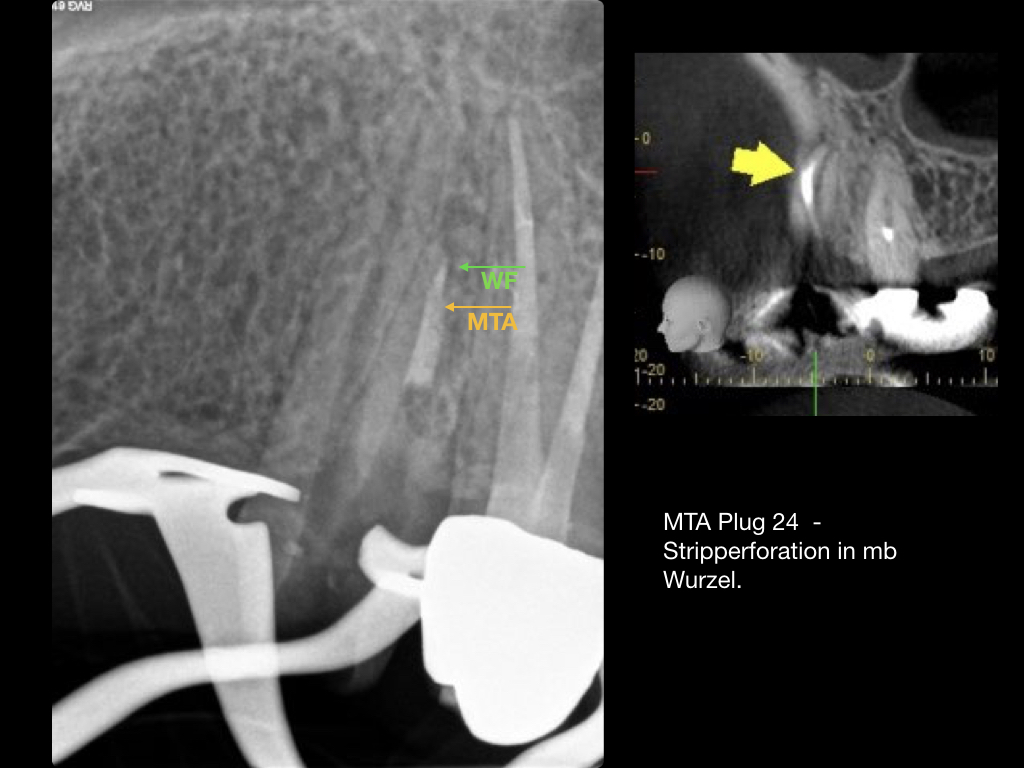

Es ist zu sehen … (2)